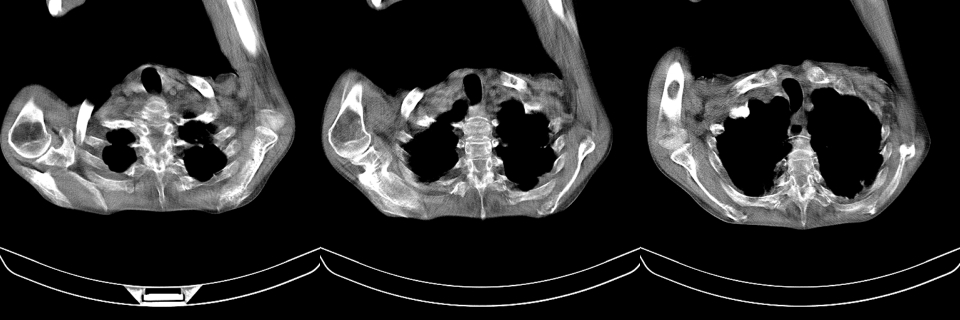

以下是引用mzh123在2007-8-26 19:58:00的发言:[br]两肺弥漫性斑片改变,其中可见大小不等之不规则空洞,结合既往病史还是考虑结核复发及感染。

以下是引用云翔在2007-8-26 20:54:00的发言:[br]这是44岁的肺吗?是否有先天病的基础?干酪性肺炎?